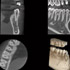

Höchste Bildqualität

X-ERA SMART verfügt über ein einzigartiges Patientenpositionierungssystem im 3D Bereich, das jede Bildverzerrung durch Patientenbewegung komplett ausschließt. Das Technologiekonzept erzeugt eine Bildqualität in extrem hoher Auflösung. Zwei verschiedene Aufnahmegrößen mit einer Voxel Größe von 80μm / 100 μm liefern in jeder Sichtfeldgröße (FoV) exzellente Ergebnisse für die weitere Diagnostik und Behandlung.

Nacholgend ein paar phänomenale Bilder & Werte,

die nicht nur einem Fachmann die Sprache verschlagen:

Aufnahmeparameter: Ceph LA; 82 kV; 10 mA; 8.0 s; 0.8 mm CU + 6.0 mm AL

gemessene Dosis: 2.99 µGy